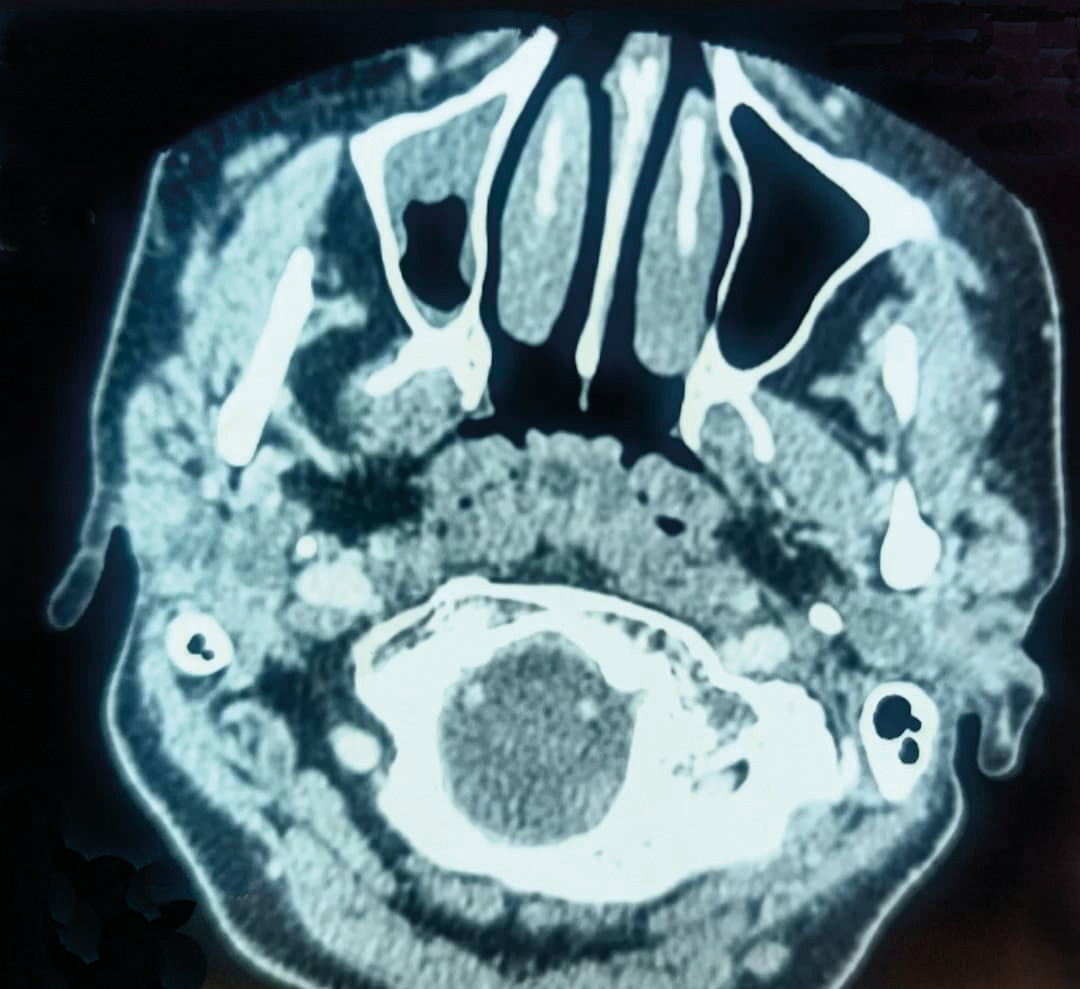

Une patiente âgée de 40 ans est admise à l’hôpital pour exploration d’adénopathies cervicales. L’interrogatoire révèle une obstruction nasale chronique accompagnée d’une rhinorrhée. L’endoscopie met en évidence une rhinite croûteuse avec un bombement du cavum (fig. 1). La tomodensitométrie montre un cavum pseudotumoral (fig. 2, 3 et 4). L’histologie objective un processus granulomateux tuberculoïde (fig. 5). Le GeneXpert sur fragment de biopsie, l’intradermoréaction à la tuberculine et la recherche de bacille de Koch dans les crachats sont négatifs.

La calcémie, la protéine C-réactive (CRP), l’angiotensine convertase et le bilan immunologique sont normaux. La confrontation des données cliniques, radiologiques, histologiques et biologiques retient le diagnostic de sarcoïdose. L’évolution a été favorable sous corticothérapie systémique.